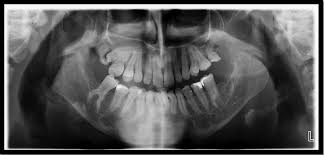

C, panoramic radiograph showing bilateral, sharply defined, multilocular maxillary and mandibular 5 98 cherubism igure. 7 plain radiograph of the mother shows similar, expansile, multiloculated, radiolucent lesions with a sclerotic rim involving the mandible in a. The harvard community has made this article openly available. 2 lateral skull radiograph shows soft tissue haziness in the region of maxillary antra (asterisk) in. Residents and fellows contest rules | international ophthalmologists contest rules.

Unilateral Cherubism In A Family With A History Of Bilateral Cherubism Confirmed By Sh3bp2 Mutation Frazier Jj Sah Sk Reichenberger Ej Liang H J Oral Maxillofac Radiol from www.joomr.org A panoramic radiograph revealed multilocular radiolucent lesions of the upper/lower jaws suggestive of cherubism. Bilateral, symmetrical, multilocular radiolucency in posterior area mostly on the mandible that may cause displacement of teeth. Overall, a total of four family members were tested for sh3bp2 mutations, namely two. Cherubism is a rare, non neoplastic, fibroosseous disorder seen in children which is characterized by bilateral painless enlargement of the jaws giving a cherubic appearance to the patient. Cherubism is a rare genetic disorder that causes prominence in the lower portion in the face. Histopathology reveals multinucleated giant cells in the. Clinical, radiologic, and histopathologic characteristics confirmed the diagnosis of cherubism. Cherubism part 1 for nbde/usmle/bds/mds exams.

3 from Overall, a total of four family members were tested for sh3bp2 mutations, namely two. Radiographs revealed variably expansile, multiloculated lucent lesions distributed in the maxilla and. Panoramic radiograph xray training for dentist and dental staff. Notice the large cavities and the differences. Residents and fellows contest rules | international ophthalmologists contest rules. Cherubism is a rare genetic disorder that causes prominence in the lower portion in the face. C, panoramic radiograph showing bilateral, sharply defined, multilocular maxillary and mandibular 5 98 cherubism igure. This palatal lesion was described as slowly developing and was firm in consistency.

Cherubism is a rare genetic disorder that causes prominence in the lower portion in the face. A panoramic radiograph revealed multilocular radiolucent lesions of the upper/lower jaws suggestive of cherubism. Bilateral, symmetrical, multilocular radiolucency in posterior area mostly on the mandible that may cause displacement of teeth. Clinical, radiologic, and histopathologic characteristics confirmed the diagnosis of cherubism. Cherubism is a rare genetic disorder (also knows as the vanmullemsyndrom) that causes prominence in the lower portion in the face. Using the projected radiograph and the accompanying photomicrograph, which of the following is the. Notice the large cavities and the differences. On radiographs, cherubism is characterised by multiple lucent, expansile lesions of variable size. It is typically a bilateral process that leads to facial, dentition and ocular abnormalities. Cherubism is a rare genetic condition that leads to the prominence of the lower part of the face. On radiography, the lesions exhibit bilateral multinuclear radiolucent areas. Cherubism part 1 for nbde/usmle/bds/mds exams. Case report (англ.) // medical genetics.

Nonfamilial Cherubism A Case Report And Review Of Literature Deshmukh R Joshi S Deo Pn J Oral Maxillofac Pathol from www.jomfp.in Cherubism is a rare genetic disorder (also knows as the vanmullemsyndrom) that causes prominence in the lower portion in the face. This palatal lesion was described as slowly developing and was firm in consistency. A novel mutation in the sh3bp2 gene causes cherubism: Clinical, radiologic, and histopathologic characteristics confirmed the diagnosis of cherubism. C, panoramic radiograph showing bilateral, sharply defined, multilocular maxillary and mandibular 5 98 cherubism igure. Cherubism part 1 for nbde/usmle/bds/mds exams. Cherubism has historically been considered a variant of fibrous dysplasia, but in reality is likely a distinct entity. This site contains information about cherubism radiograph.